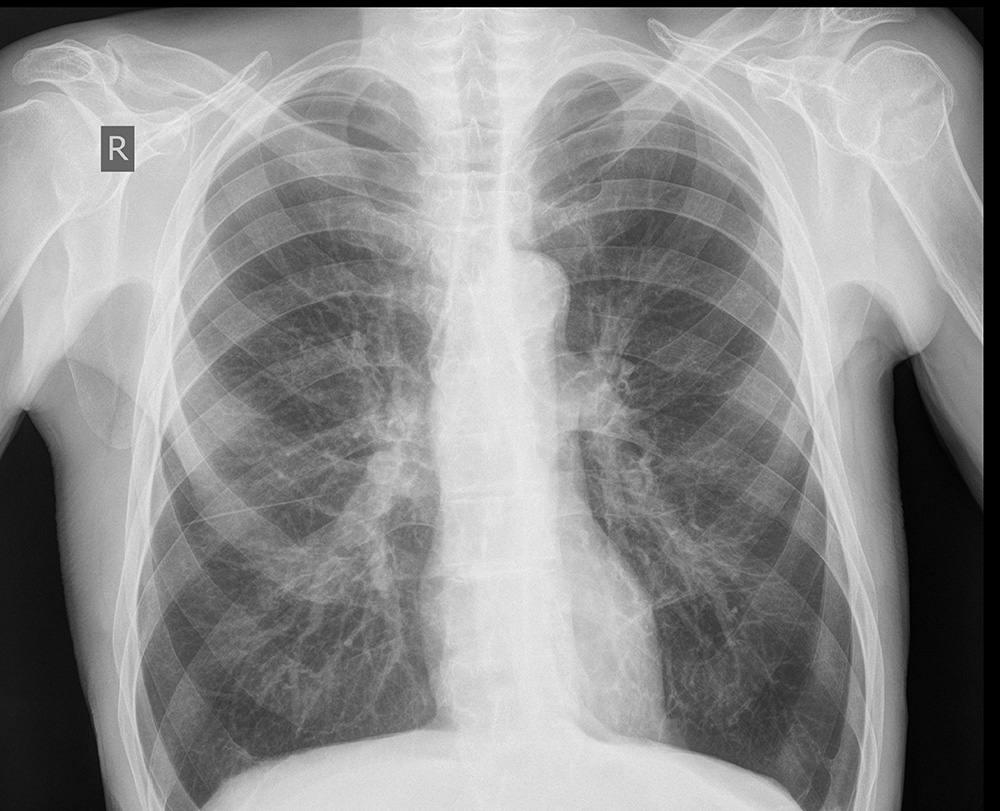

Рентгеновские снимки плат в высоком разрешении